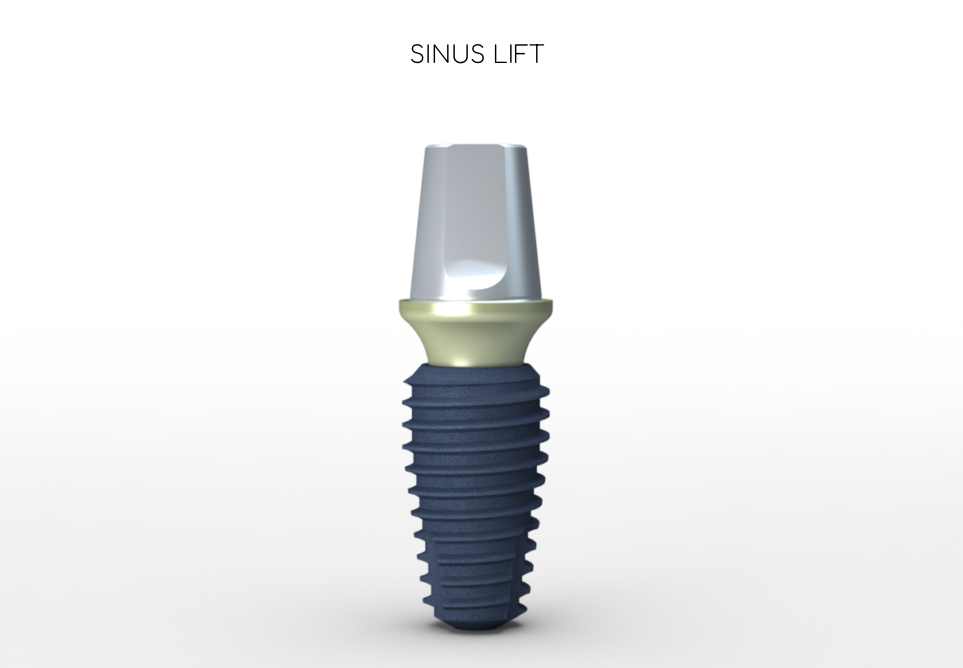

– Un trattamento del canale radicolare eseguito correttamente salva un dente, che altrimenti dovrebbe essere estratto e successivamente sostituito da un impianto dentale o da un lavoro dentale. Negli ultimi anni, il miglioramento dei metodi di trattamento endodontico ha portato a una riduzione del numero di denti estratti. Sempre più denti distrutti o infetti vengono mantenuti sull’arco oggi, a causa delle prestazioni ottenute dai trattamenti canalari.